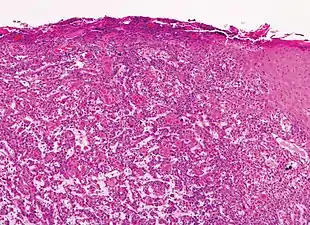

Histopathologically, the epidermis in SCC in situ (Bowen’s disease) will show hyperkeratosis and parakeratosis. There will also be marked acanthosis with elongation and thickening of the rete ridges. These changes will overly keratinocytic cells which are often highly atypical and may in fact have a more unusual appearance than invasive SCC. The atypia spans the full thickness of the epidermis, with the keratinocytes demonstrating intense mitotic activity, pleomorphism, and greatly enlarged nuclei. They will also show a loss of maturity and polarity, giving the epidermis a disordered or “windblown” appearance.

Two types of multinucleated cells may be seen: the first will present as a multinucleated giant cell, and the second will appear as a dyskeratotic cell engulfed in the cytoplasm of a keratinocyte. Occasionally, cells of the upper epidermis will undergo vacuolization, demonstrating an abundant and strongly eosinophilic cytoplasm. There may be a mild to moderate lymphohistiocytic infiltrate detected in the upper dermis.[33]

Histopathology of squamous cell carcinoma in situ (black arrow), compared to normal skin, showing marked atypia.

Squamous cell carcinoma in situ, showing prominent dyskeratosis and aberrant mitoses at all levels of the epidermis, along with marked parakeratosis.[33]